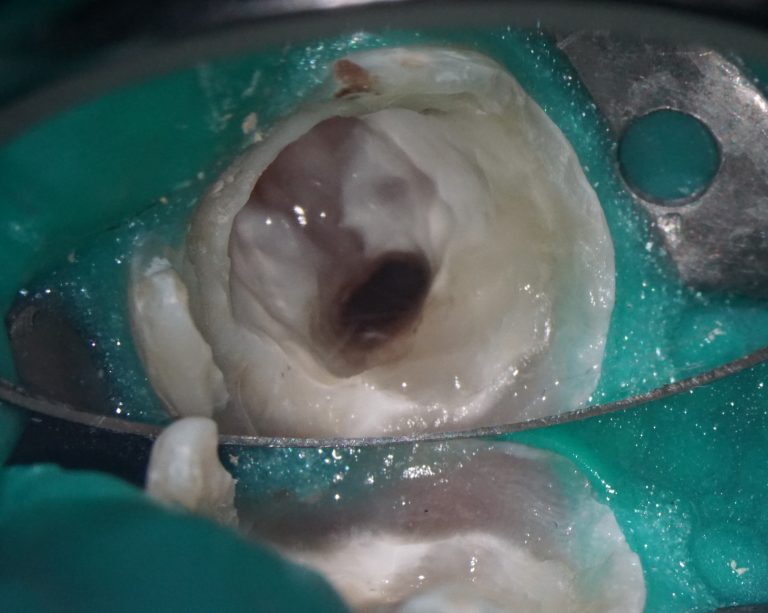

During a clinical examination, it is difficult to verify the presence of caries located under a filling, which is why the information obtained during a radiological examination is so important

Please note that despite the fact that the radiolucent area is poorly visible when viewing CBCT, Diagnocat reflected in the report the presence of signs of caries and accurately indicated the localization